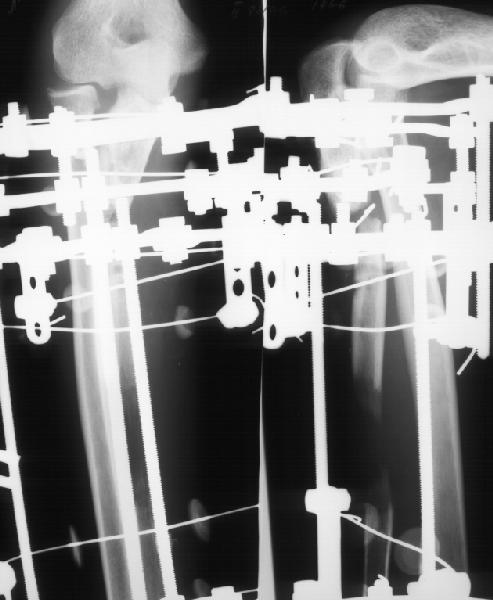

Мужчина 34 лет получил открытый перелом локтевой кости в апреле 1997 г. Через 2 недели - остеосинтез пластиной в местной больнице.Через 8 мес. пластика по Хахутову. В январе 2000 г. - аутопластика из крыла подвздошной кости. Трансплантат рассосался. С декабря 2001 г.наблюдается в институте. В январе 2002 г. - удаление пластинки, резекция концов отломков, остеотомия дистального отломка, дистракционный остеосинтез по Илизарову. Проводилась дистракция по 0,5 мм/сут., с перерывами на 10-14 дней.

Ввиду слабой регенерации темп уменьшен до 0,25 мм/сут. Дистракция закончена в июле 2002 г (см. приложение 1). Декабрьский снимок (приложение 2) показывает лизис концов отломков, замедленную перестройку регенерата.